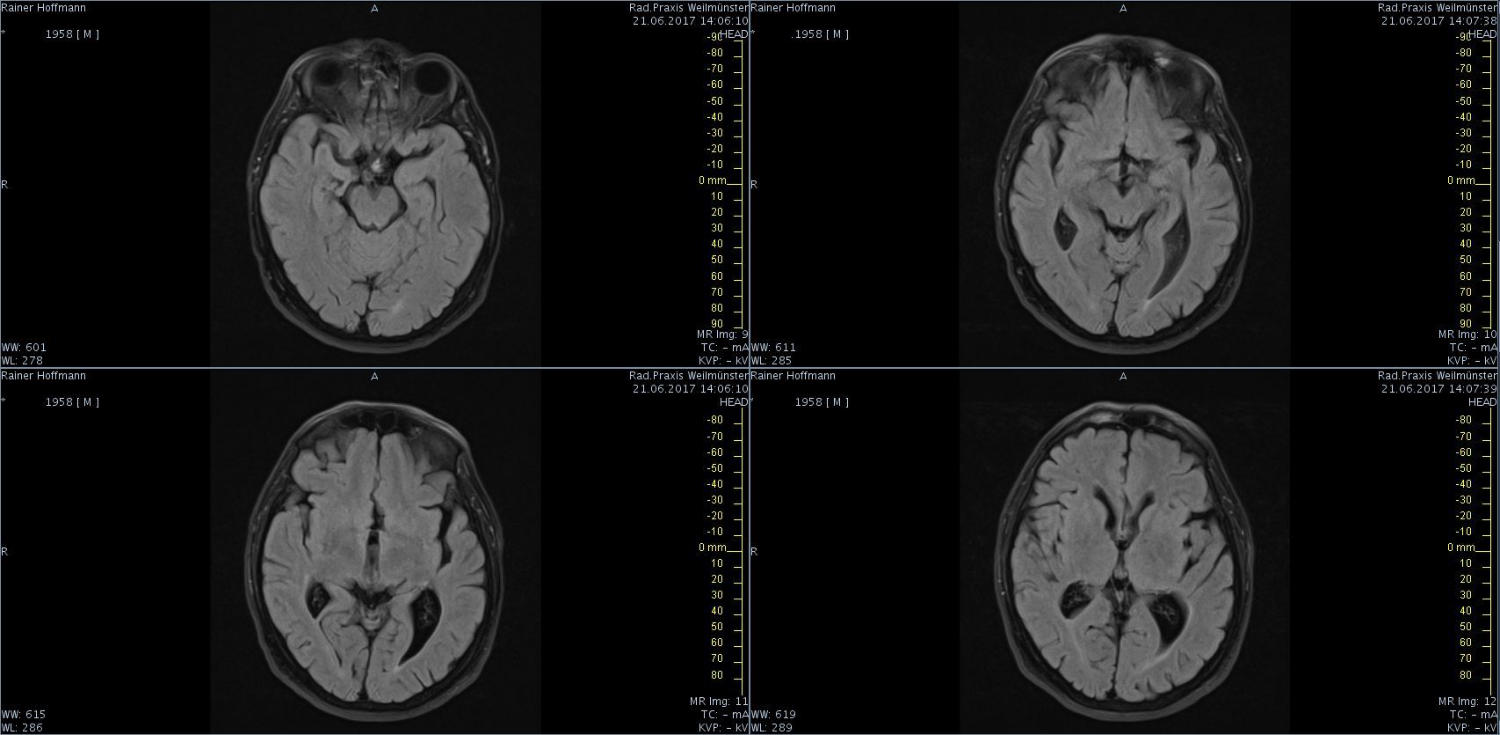

Das ist ja ganz toll, dass Ihr die Seite so schnell gefunden habt. Ich zeige euch jetzt ein ganz, ganz anderes Paßfoto von mir. Es könnte Ähnlichkeiten zu anderen lebenden oder bereits verstorbenen Personen geben. Wenn Ihr das erste Bild oben links anklickt wird es ver- größert dargestellt. Dann kann man mit den Pfeiltasten am unteren Bild- rand durch meinen Kopf blättern. Es gibt nicht viel zu sehen. Vielen Dank an Martina für Ihre Hilfe.

MRT